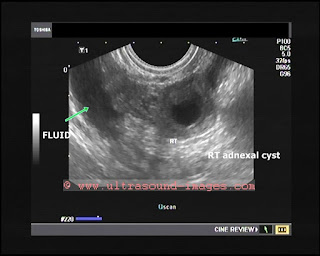

Looks like Rt. ectopic gestation in 5 weeks amennorhoea.

=Thick walled cystic lesion of 2.5 cms.

= plenty of free and organized fluid in cul de sac and surrounding regions

= empty uterine cavity